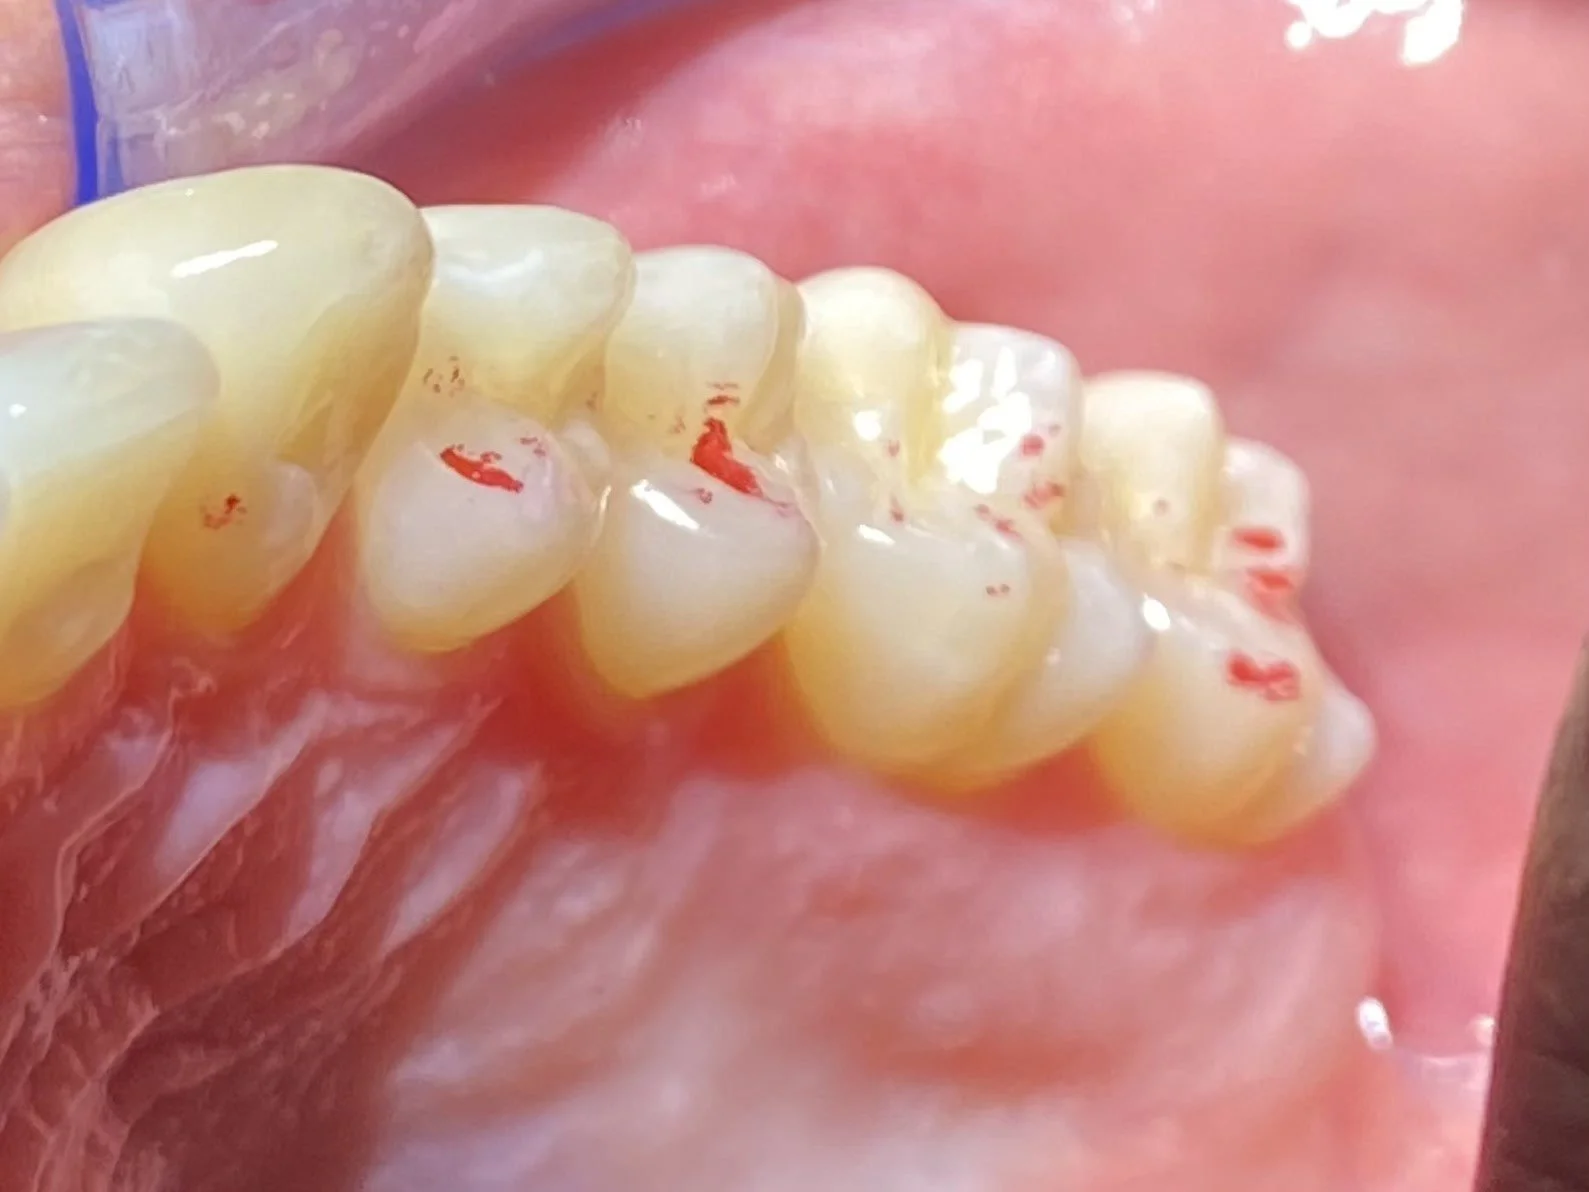

PROTECTIVE COMPOSITE RESIN OVERLAYS FOR BIO-DESIGNING LEFT AND RIGHT JAW MOVEMENTS